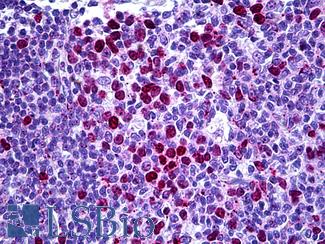

PDL1 (CD274)

Anti-B7-H1 / PD-L1 / CD274 antibody IHC staining of human testis. Immunohistochemistry of formalin-fixed, paraffin-embedded tissue after heat-induced antigen retrieval. Antibody LS-B10562 dilution 1:100.

PD1 (PDCD1 / CD279)

Anti-CD279 / PD-1 antibody IHC of human tonsil. Immunohistochemistry of formalin-fixed, paraffin-embedded tissue after heat-induced antigen retrieval. Antibody LS-B7883 dilution 20 ug/ml.